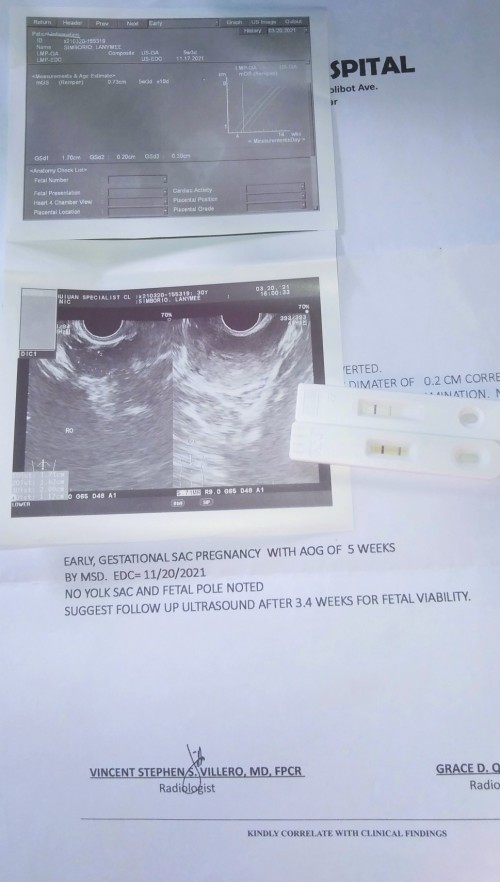

ito yung result ko sa check up ko nong March 20.

Magbasa paThen ito nong balik ko nong April 10 😔😔😔 wala na. excited pa naman partner ko, nanay at mga kapatid nya .